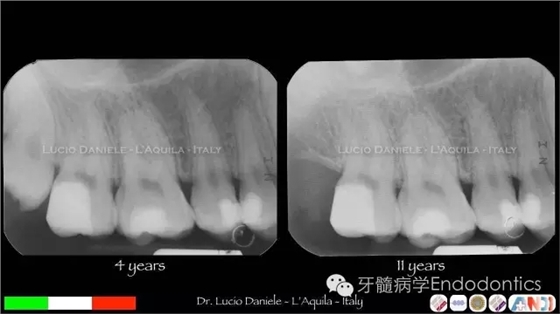

圖8.隨訪4年、11年